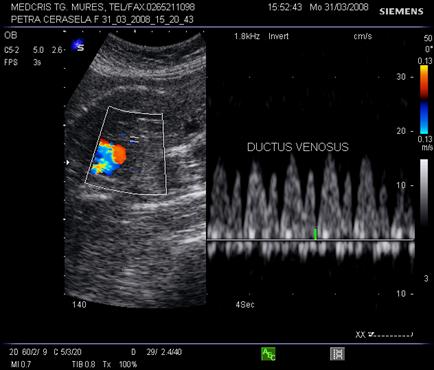

Ductul venos

In sectiune sagitala ductul venos apare ca o continuare a venei ombilicale spre vena cava inferioara. Inclinatia creste de la 7 la 48 la locul de unire cu vena cava. Aspectul este de "trompeta" de la circa 17 saptamani.[14,17]

Fig.nr. 328. Schema ductului venos( cu doua sageti, sageata unica indica directia fluxului sangvin,adaptat dupa Mihu[17] )

Aspectul eco Doppler normal in ductul venos este de sistola ventriculara, diastola ventriculara, contractie atriala, deci aspect trifazic.

Ductul venos creaza o comunicare intre sistemul venos periferic ombilical si sistemul venos central al fatului. Gradientul presional in ductul venos se modifica in caz de suferinta fetala.

Daca are loc centralizarea circulatiei, prin scaderea presiunii venoase centrale, scade presiunea in ductul venos in timpul contractiei atriale, cu aparitia reverse - flow.( unda a negativa ) [19]

Fig. nr.329. Ductus venosus( sageata ) la o sarcina de 16 sapt,. sectiunea sagitala fetala

Fig. nr. 330. Ductus venosus la doppler pulsat cu CFM , la o sarcina de 27 sapt. Se remarca aspectul normal trifazic al undei .